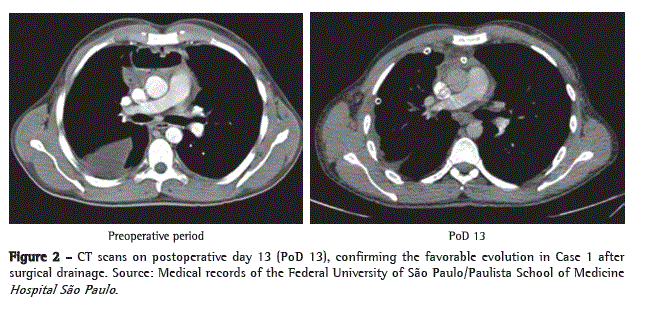

We opted for therapy with broad-spectrum antibiotics (imipenem, cilastatin, and vancomycin) and emergency surgical exploration. The patient was placed in a semi-seated position, with outstretched arms, and his RHT was elevated 30° with the use of cushions. We opted for simple orotracheal intubation. We began with collar cervicotomy at the level of the cricoid cartilage to explore cervical compartments and continued to explore up to the base of the mandible, from where the infectious focus originated. Subsequently, we performed a 1.5-cm thoracotomy incision in the seventh right intercostal space (RIS), introduced a 10-mm fiberoptic bronchoscope (30°), and performed a 6.0-cm accessory anterior minithoracotomy incision in the fourth RIS, through which the entire pleural cavity was cleaned, the mediastinal pleura was opened, and all purulent fluid was drained. We placed an 18 F tube (airtight seal) in the anterior mediastinum and two tubes (water seal) in the pleural cavity-a posterior 18 F tube and an anterolateral 28 F tube. In the cervical region, we placed a Penrose drain, creating communication between the surgical site and the anterosuperior mediastinum, as well between the surgical site and the right pleural cavity, through the pretracheal fascia. Subsequently, the patient was referred to the ICU, where he remained under mechanical ventilation and received low doses of vasoactive drugs. The evolution was favorable, mechanical ventilation and the use of vasoactive drugs were discontinued on postoperative day 2, and the patient was discharged from the ICU on postoperative day 3 (Figure 2). The patient was

discharged from the hospital in good general health on postadmission day 18, without the need for further surgical intervention (Figures 3a and 3b).